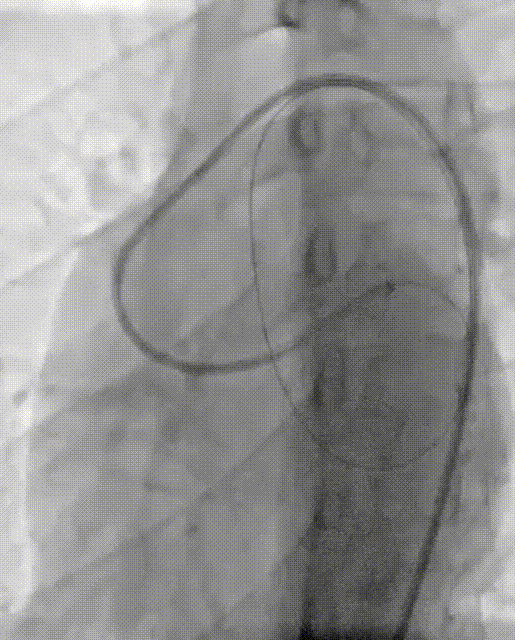

释放16mmAVP-II血管封堵器

术后造影提示封堵器位置良好